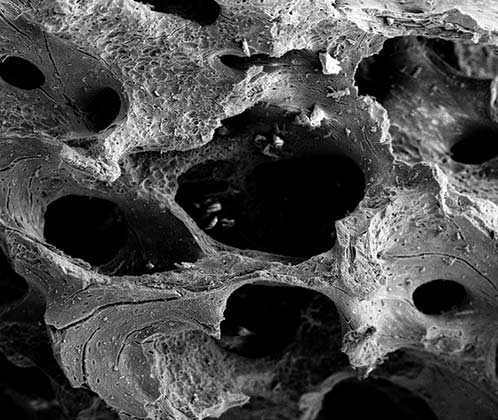

MinerOss SEM at 25x

SEM at 25x

MinerOss SEM at 75x

SEM at 75x

SEM images of MinerOss XP illustrate a structure that is similar to a natural bone mineral and is highly porous to provide more space for new bone deposition and a rough surface which facilitates cell adhesion and spread for bone in-growth.2